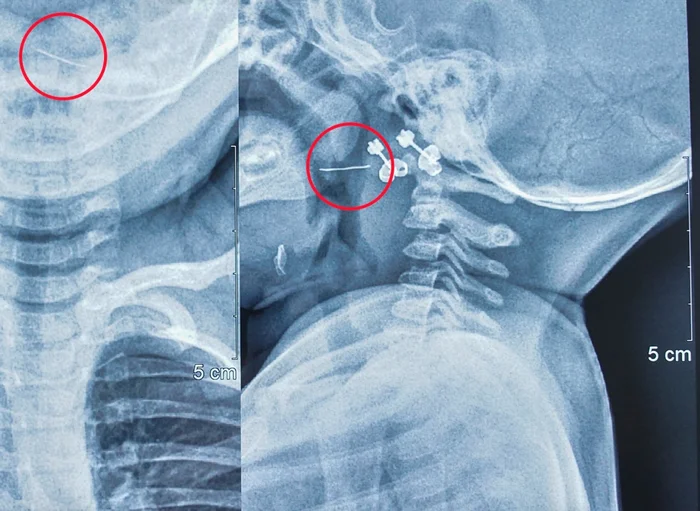

Tại đây, trẻ được các bác sĩ chỉ định chụp X-Quang cổ ngực thì được chẩn đoán theo dõi dị vật kim loại vùng sàn họng – miệng và chuyển đến Bệnh viện Nhi Trung ương để tiếp tục điều trị.

Tại Bệnh viện Nhi Trung ương, sau khi trẻ được thăm khám, soi họng và đọc kết quả phim X-Quang, các bác sĩ xác định có dị vật kim loại đâm xuyên qua Amidan bên trái của trẻ.

Bác sĩ Nguyễn Khắc Trưởng, khoa Tai - Mũi - Họng, Bệnh viện Nhi Trung ương, người trực tiếp gắp dị vật cho bệnh nhi cho biết: “Nhận thấy dị vật mắc ở vị trí phức tạp, nguy cơ chảy máu cao, chúng tôi đã nhanh chóng cho trẻ làm các xét nghiệm cần thiết rồi chuyển lên phòng mổ, gây mê và tiến hành gắp dị vật lấy ra được sợi thép nhỏ nhưng rất cứng và nhọn 2 đầu, dài 2cm”.

Sợi thép này đâm xuyên từ cực trên xuống cực dưới Amidan bên trái của trẻ. May mắn là dị vật chưa xuống sâu hơn nên không gây nguy hiểm đến tính mạng của trẻ. Nếu không được gắp ra kịp thời, đoạn kim loại này có thể gây nhiễm trùng và chảy máu, dẫn đến những hậu quả khó lường.